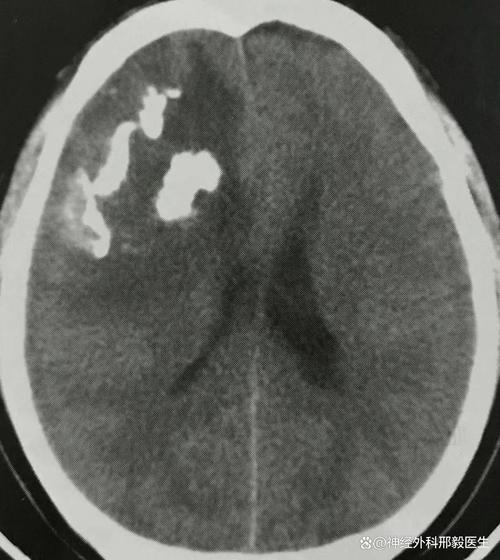

- 头颅CT(计算机断层扫描):最快、最基础的检查,可以快速判断是否有脑出血、大面积脑梗塞、肿瘤占位效应和颅骨骨折,但对于小的胶质瘤和早期脑梗,CT可能不敏感。